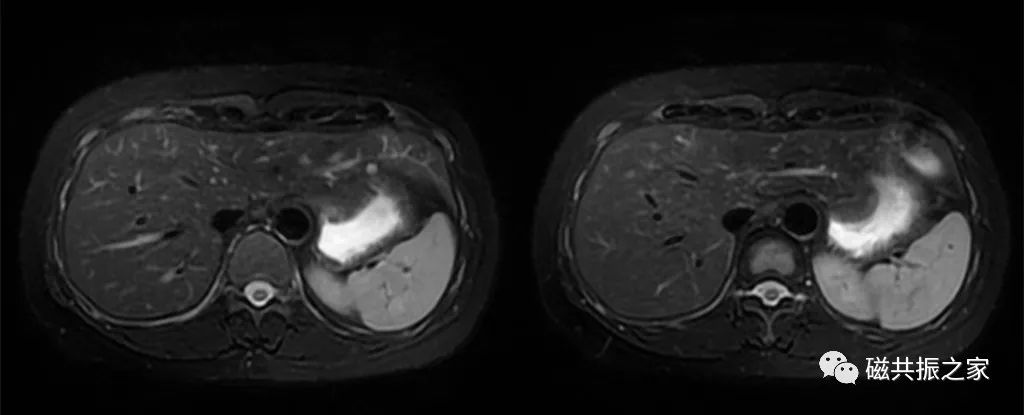

横轴面:横轴面同反相位序列

在矢状位和冠状位上定位。扫描范围包括整个肝脏,根据扫描范围合理调整扫描范围,需包括整个病变范围。

| 梯度回波水脂分离序列 | LAVA-FLEX | mDixon XD FFE | Dxion_VIBE | WFI-quick |

水中的氢质子与脂中氢质子相差3.27ppm,140Hz/T。1.5T上反相位2.4ms 同相位4.8ms,3.0T上反相位1.2ms 同相位2.4ms。

同反相位序列主要用于检测病灶含脂质情况,如脂肪肝,铁过载的鉴别诊断。

对于微小含脂类病变,3D薄层的可靠性更高。

| 脂肪定量分技术 | Ideal IQ | mDIXON Quant | Liver Lab | FACT |